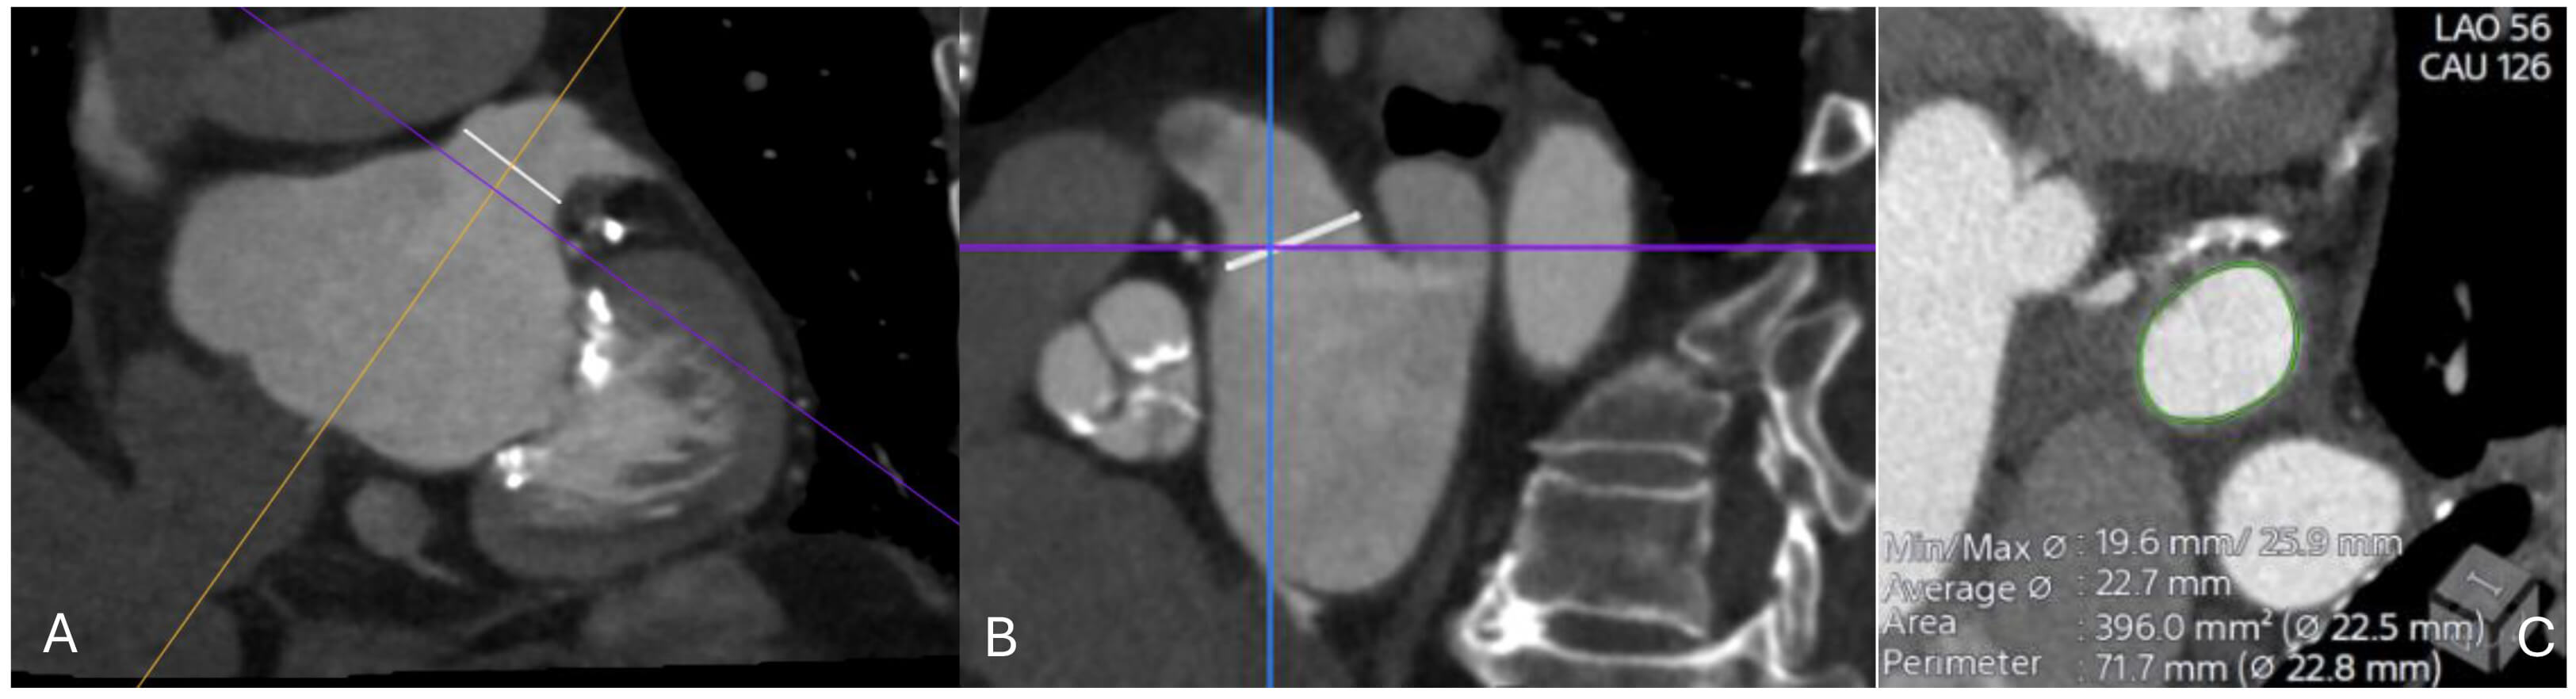

The first step in pre-procedural evaluation is exclusion of LAA thrombus. TOE remains widely used for this purpose, but contrast-enhanced CT with delayed imaging (typically 60–90 seconds post-contrast) has demonstrated high sensitivity and specificity for differentiating thrombus from slow flow. CT is particularly valuable for characterizing LAA morphology. It allows classification into common morphotypes (chicken wing, windsock, cactus, cauliflower), which have been linked to procedural feasibility and risk of residual leaks. CT characterizes LAA morphology and landing-zone geometry, as summarized in Tables 4,5 [111]. These measurements directly inform device sizing (Fig. 7). For example, the Watchman FLX typically requires oversizing of 10–20% relative to landing zone diameter, while the Amplatzer Amulet requires assessment of both ostial and landing zone diameters for appropriate sizing. Peripheral access evaluation is also essential, particularly in patients with peripheral vascular disease. CT allows assessment of iliofemoral access in the same dataset used for cardiac anatomy.

Fig. 7.

CT imaging assessment of the left atrial appendage (LAA) prior to percutaneous closure. (A) Oblique multiplanar reconstruction demonstrating the ostium of the LAA (white line), aligned along the true anatomical axis. (B) Orthogonal cross-sectional view showing the same ostial measurement (white line) in the perpendicular plane. (C) Cross-sectional reconstruction at the level of the ostium with automated contouring (green) and derived measurements of minimal and maximal diameters, average diameter, area, and perimeter (22.5–22.8 mm). These values are used for device sizing and procedural planning.

TOE offers real-time imaging and thrombus detection and traditionally has been used for the evaluation of the LAA and the proper device selection. However, TOE is limited by its two-dimensional nature and dependence on operator skill. CT, with its isotropic spatial resolution, enables precise reconstruction of the LAA ostium and landing zone in multiple planes, reducing under- or over-sizing, while can offer simulation of the device in MPR to confirm sealing [112]. It also delineates complex or multilobed appendages, where TEE may underestimate dimensions. In clinical practice, many centres use a hybrid approach with a TEE for thrombus exclusion and peri-procedural guidance, and CT for device planning. Increasingly, CT alone is being adopted for both pre-procedural planning and post-procedural follow-up, particularly as delayed phase protocols gain acceptance for thrombus evaluation.